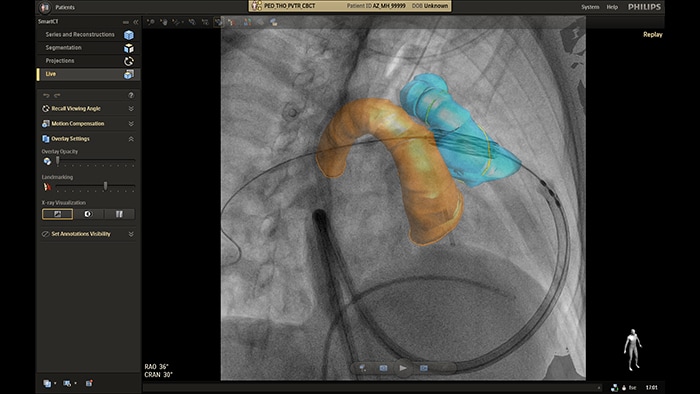

Prowadzenie pod kontrolą obrazowania w czasie rzeczywistym z użyciem aplikacji SmartCT

Automatyczna analiza naczyń na obrazie angiografii rotacyjnej z użyciem aplikacji SmartCT